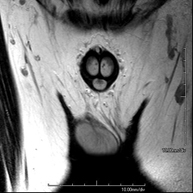

Prova diagnòstica no invasiva que consisteix en l'obtenció d'imatges d'alta definició anatòmica de la pelvis mitjançant l'ús d'un camp electromagnètic i ones de ràdio (amb un emissor i un receptor). No utilitza radiació ionitzant. Es realitza per a l'estudi de patologies d'úter, d'ovari, de trompes i de vagina, ja siguin d'origen tumoral, inflamatori o vascular. També permet valorar les estructures adjacents localitzades a la pelvis i la identificació de les seves alteracions. De vegades és necessari l'ús de contrast intravenós (Gadolini) per caracteritzar les lesions. - RM Pelvis masculina

Prova diagnòstica no invasiva que consisteix en l'obtenció d'imatges d'alta definició anatòmica de la pelvis masculina mitjançant l'ús d'un camp electromagnètic i ones de ràdio (amb un emissor i un receptor). No utilitza radiació ionitzant. No requereix preparació prèvia. En algunes ocasions necessita l'ús de contrast paramagnètic (Gadolini) per caracteritzar les lesions. Aquesta prova permet valorar òrgans com la bufeta urinària, la unió entre els urèters i la bufeta, la pròstata, les vesícules seminals, la uretra i els ossos de la pelvis, entre d'altres. - RM de Fetge

Prueba diagnóstica no invasiva que consiste en la obtención de imágenes de alta definición anatómica de la región escrotal mediante el empleo de un campo electromagnético y ondas de radio (con un emisor y un receptor). No utiliza radiación ionizante. En ocasiones se deberá emplear contraste paramagnético (Gadolinio) para completar el estudio. Se utiliza para el estudio detallado de los testículos, para identificar posibles tumores u otras patologías, además de poder visualizar alteraciones de las estructuras adyacentes. - RM Peneana